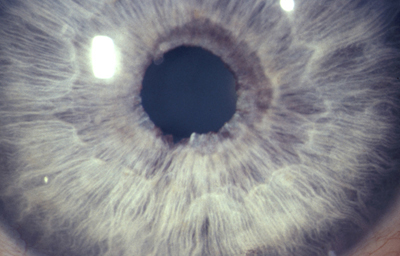

Anomalias del Estroma: Hiperplasia, Hipoplasia

Hipoplasia

Archivo fotográfico Dr. Francisco Barraquer.